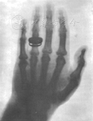

在伦琴发现X射线后的第4天,就有报道"一家医院曾应用伦琴射线在荧光屏上观察到一根进入患者手掌中的铁针,并顺利地取了出来"。1895年12月22日,伦琴将荧光纸板改换为照相干板,并简单拍摄了自己妻子戴有戒指的掌指骨,这是人类历史上第一张X射线照片(图2)[3]。1896年1月1日,伦琴将他拍摄的一些X射线片送给他的朋友们欣赏,这引起了全世界的震动,此后也引起过恐慌,当时传说X射线可以穿透妇女的衣服而窥视到人体内部。